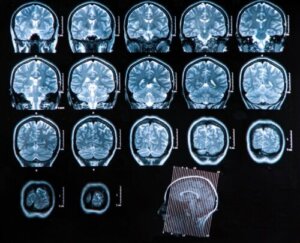

- Computed tomography: This has great diagnostic usefulness, as it allows you to check any links with the medical condition, and establish treatment according to the corresponding phase. This technique is also a good study to follow up the evolution of the pathology after the implementation of the treatment.

- Magnetic resonance imaging: This is the best type of imaging study in the diagnosis of brain abscess. It’s much more sensitive than computed tomography and offers many advantages in the detection of early cerebritis, and edema and better differentiation between areas of inflammation and other affected structures.